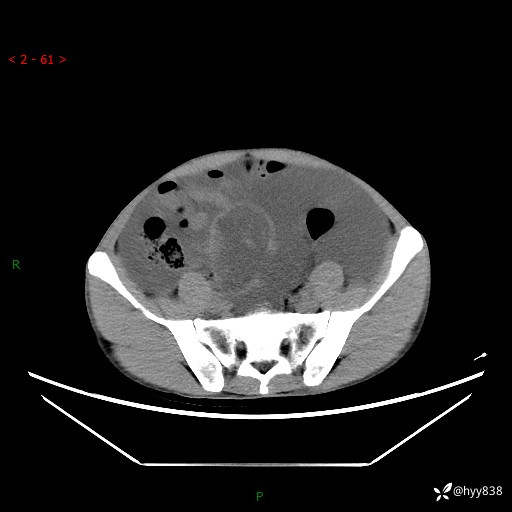

现病史:患者10天前无明显诱因出现腹部胀痛不适,无畏寒发热,无胸痛胸闷,无心慌气短,无恶心呕吐,无腹泻及黑便,无粘液血便及里急后重等症状,4天前在当地县人民医院就诊,行腹部CT示:下腹部占位性病变,腹腔及盆腔积液;今患者为求进一步诊治来我院治疗,门诊以“腹水”收治入院。 发病以来,精神饮食可,大小便正常,体重体力无明显变化。

腹部CT平扫+增强